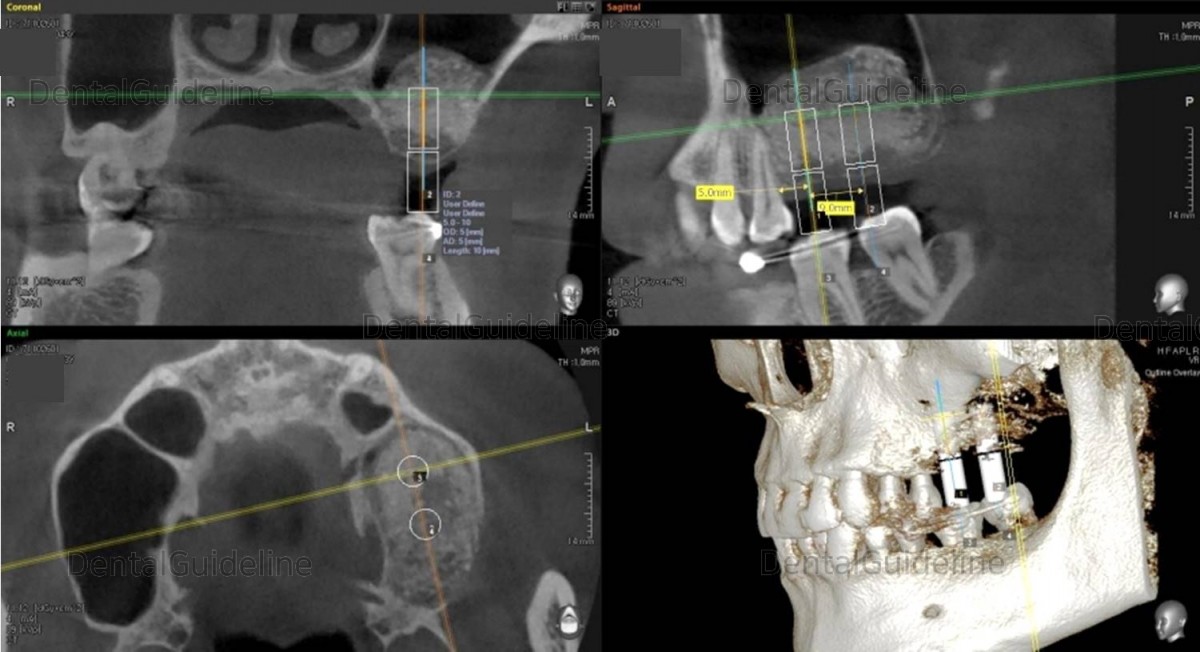

13. 3.5 months after the graft, A simple simulation of implant placement was performed using CT.

14. 2 implants were placed.

16. Panoramic radiograph after implant placement. (5*10mm, 5*11.5mm)